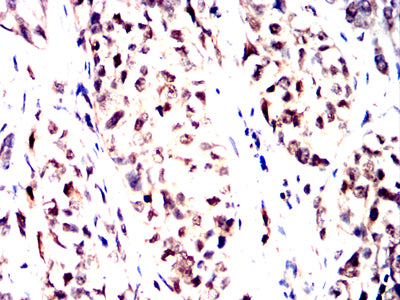

Product Image

- Immunohistochemical analysis of paraffin-embedded human bladder cancer tissues using NPM3 mouse mAb with DAB staining.